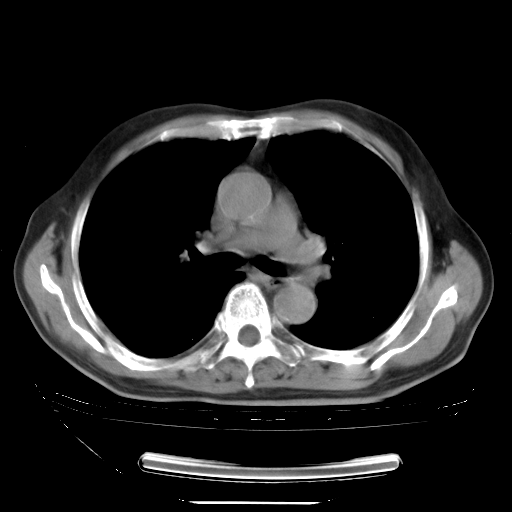

今天复查肺部CT,发现双肺广泛磨玻璃样改变。所以我把3月19日和5月9日相隔50天的肺部CT上传。请大家会诊。

2009年3月19日肺部CT片。

5月9日肺部CT(在4月27日齐鲁医院肺部CT描述部分肺组织磨玻璃样改变,12天后肺组织广泛磨玻璃样改变)